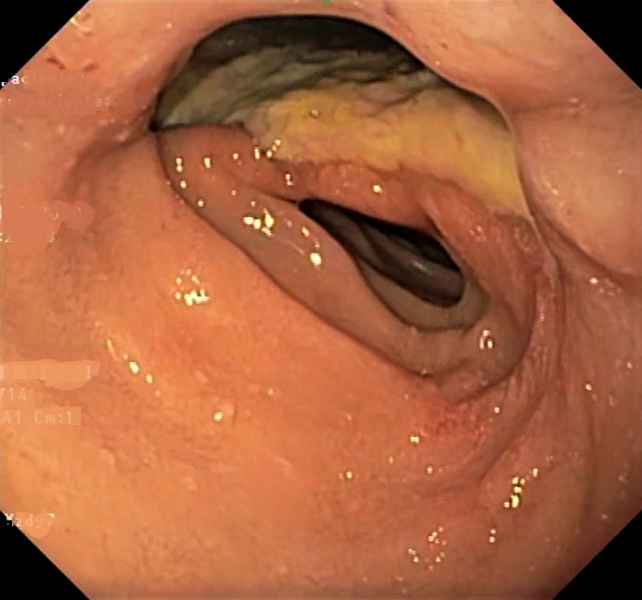

Endoscopic marsupialization of duodenal duplication cysts